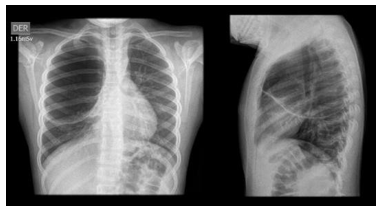

The soft tissue ultrasound of the scalp reported three collections with a total volume of 26 cc, and the gluteal ultrasound reported a small collection of 1cc. The chest x-ray showed an image of a radiolucent cyst in the apex of the right lung and middle lobe atelectasis. (Figure 1) A chest CT scan showed cystic lesions involving the right upper lobe and the segments of the left lobe, with bronchiectasis. (Figure 2)

Figure 1 Chest X-Ray.